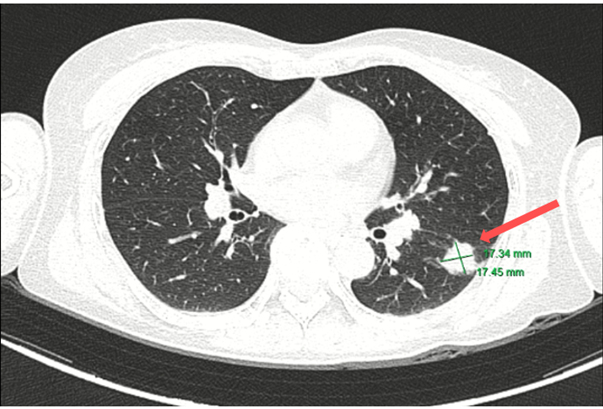

CT ngực (05/2024):

Hình 2: Hình ảnh tốt đặc ở phân thùy S6 phổi trái, đường kính 17 mm, bờ tua gai. Không thấy hạch trung thất to.